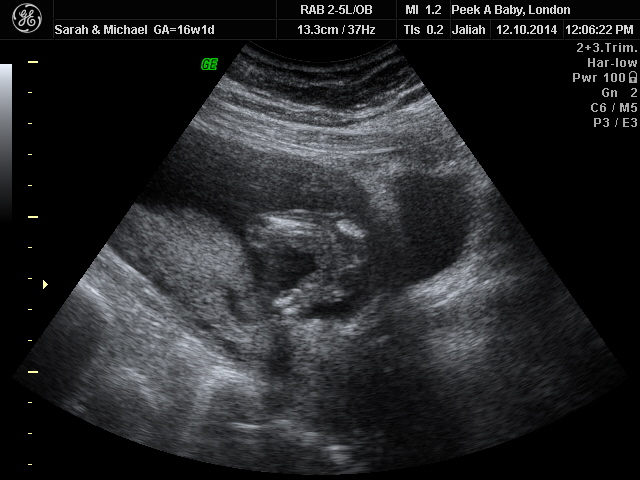

Private gender scan said GIRL but not sure.... Please give me you opinion :)